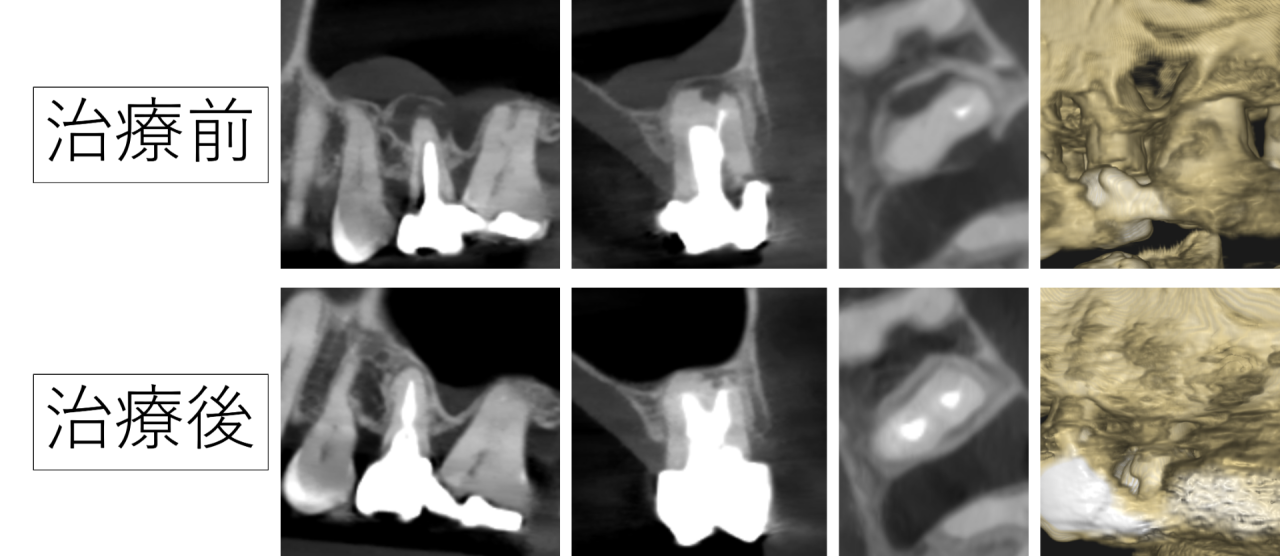

左上の5番目の歯の根の先に黒い影があります。これは炎症により骨が溶けている部分です。

炎症が骨を溶かして貫通し、上顎洞という鼻の部分(副鼻腔)にまで影響しています。上顎洞も炎症を起こしています(副鼻腔炎)。

顎の骨も根の病気の炎症で溶け、貫通し穴が開いてしまっています。患者様は驚かれましたが、できるだけ歯を残したいとご希望されたので、精密な根管治療を行うことにしました。

2年半後、CTを撮影し状態を確認したところ、根の病気は治り溶けた骨が再生していました。鼻(上顎洞)に起きていた炎症も無くなっています。

貫通した穴も治っていました。患者様は非常に喜ばれました。本当に良かったです。